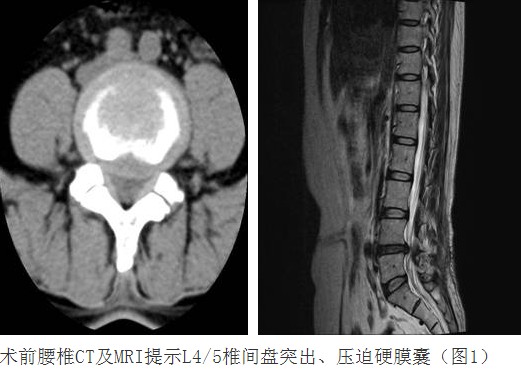

腰椎间盘突出症发病率高、是腰腿痛最常见的原因之一,部分病人保守治疗可以缓解病情得以控制;部分病人由于突出髓核压迫神经根,可致神经根变性,表现为下肢无力麻痛、反复腰腿痛,如得不到有效的手术治疗,严重的可致残。传统的腰椎间盘突出症主要为后路椎板间开窗、椎间盘摘除术,或后路椎板切除减压、椎间盘摘除、经椎弓根螺钉内固定术,其缺点前者为:“复发”率高,椎间隙变窄或消失,椎管容积变窄至椎管狭窄,椎体无法融合,加快退变。后者缺点为:手术创伤大,出血多,术后恢复慢,不能早日下床活动及医疗费用高等问题。我科在谭志宏主任医师积极的临床总结及锐意探索下,借鉴国内先进脊柱技术,在惠州地区率先开展数例后路患侧椎板间开窗髓核摘除、患侧经椎弓根单侧螺钉固定、椎间Cage融合治疗腰椎间盘突出症,此术式有创伤出血少、健侧无干扰及损伤、又能恢复椎间隙高度、骨性融合防止退变及再次复发等优点,对合并椎体不稳及患侧椎管狭窄的病人效果更为确切。此项手术的成功开展填补了惠州地区空白,同时也是国内手术治疗腰椎间盘突出症先进技术,标志了我院脊柱外科又迈进了坚实而有力的一步。

病例汇报1老年女性患者,因“反复腰腿痛10年、加重伴左下肢麻痛2月”之主诉入院,术前左下肢肌力3+级,浅感觉减退。术后腰腿疼缓解,肌力及感觉恢复正常。(1、图2)

病例汇报2老年女性患者,因“反复腰腿痛10年、加重伴左下肢麻痛3年”之主诉入院,术前间断性跛行,左下肢肌力3+级,浅感觉减退。术后腰腿疼缓解,肌力及感觉恢复正常。(1、图2)